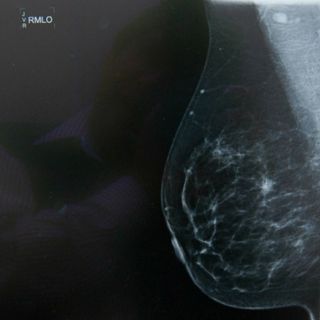

Los tumores de mama necesitan suministro de grasa para crecer

El descubrimiento podría abrir nuevas opciones terapéuticas para combatirlo

cáncer de mama necesita grasa exterior para crecer, lo que podría abrir nuevas opciones terapéuticas para combatirlo, según un estudio de un equipo español de científicos que publica Nature Communications.

El equipo, liderado por el Instituto de Investigación Biomédica (IRB) de Barcelona en colaboración con hospitales españoles y la Universidad Rovira i Virgili (URV), descubrió que las células de mama tumorales necesitan recoger grasas del exterior y trasladarlas a su interior para poder seguir proliferando.